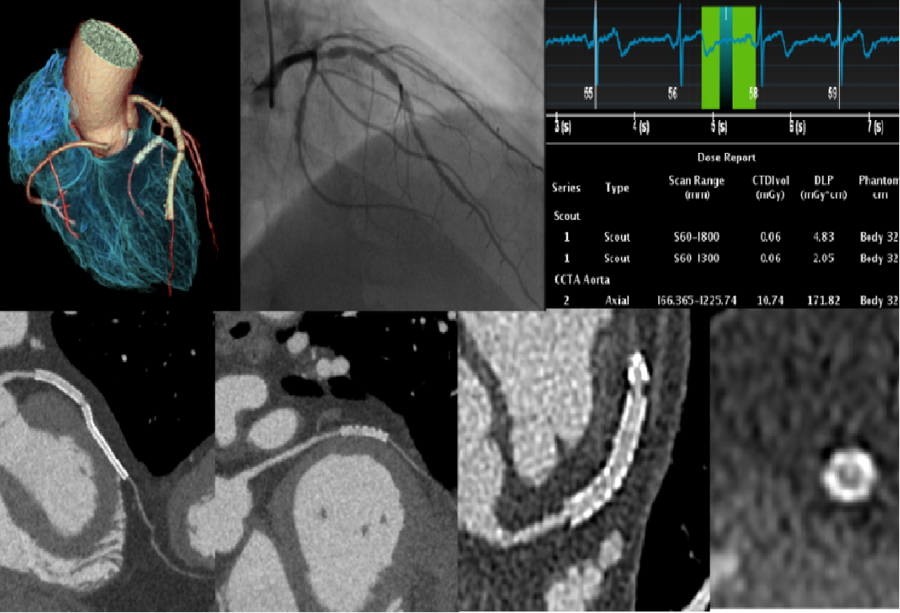

与传统的CT相比,GE 256排Revolution CT的扫描速度更快,转一圈只需要0.28秒,检查一个部位只需2.05秒的时间,做一次全身体检也只需10秒钟左右。单扇区时间分辨率为29毫秒,在任何心率和心律条件下,一个心动周期就可以获得心脏的冠脉解剖信息、斑块成分信息、心脏4D运动信息、心功能信息和心肌灌注信息。有效避免了传统CT检查容易受到心律不齐、呼吸运动、心脏搏动等因素影响,肺功能较差、心房颤动、心律不齐及老龄人可以不受限制地通过该设备完成检查。

高心率及心律不齐的情况下成像清晰稳定

冠脉支架植入术后,精确地确定支架形状、空间位置和腔内细节,实现冠脉支架高清成像

冠脉搭桥术后血管评价,16厘米宽体探测器覆盖整个桥血管范围,心脏轴扫采用 3D 蜂巢准直器和 Volume HD 宽体重建算法,极大地降低了噪声和伪影对图像的干扰,在较低辐射剂量下清晰显示桥血管、瓣膜置换情况及残存冠脉影像。

Revolution CT同时解决了心脏扫描过程中高心率、心率不齐、房颤和屏气困难等四个难题。Revolution CT在各种心率和心律条件下,只需一个心跳时间便可完成精细的心脏检查,整个成像过程不超过1秒,无需训练吸气闭气便可完成心脏冠状动脉成像。

Revolution CT颠覆传统心脏CT的诊断模式,在低剂量的前提下,一个心跳内就能同时回答心内科医生最希望了解的全部信息:冠脉是否有狭窄、心肌血供是否正常、室壁运动是否正常、心功能是否正常。此外,Revolution CT可以用四张胸片的剂量和超低造影剂用量完成冠脉成像,获得精美的图像质量。